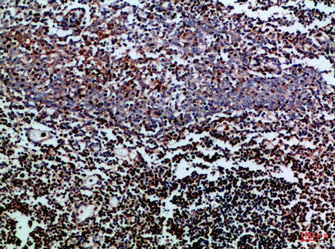

圖片:

應用范圍:IHC,ELISA

Application Recommended Dilution IHC IHC-p:1:50-300 ELISA 1:10000-20000 -

- the immunohistochemical staining patterns of CD3 and CD20 in Malignant Lymphoma Cells, were investigated. PMID: 28442514